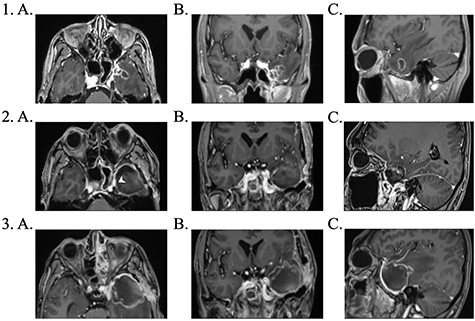

Brain magnetic resonance imaging (MRI) study with contrast revealed an irregular enhancing mass within the left temporal lobe measuring 3 × 2.6 × 2cm with significant surrounding parenchymal oedema (Fig. 1). In addition, enhancement of the adjacent dura extending to the left temporal fossa, pterygoid muscle and left sphenoid sinus was observed.

1. Pre-operative contrast enhanced brain MRI: (a) T1 axial view with enhancing lesion; (b) T1 coronal and (c) T1 sagittal. 2. First post-operative contrast enhanced brain MRI showing resection of lesion: (a) T1 axial. Arrow: dural enhancement of sphenoid sinus; (b) T1 coronal and (c) T1 sagittal. 3. Second post-operative contrast enhanced brain MRI following endoscopic re-resection: (a) T1 axial; (b) T1 coronal and (c) T1 sagittal.